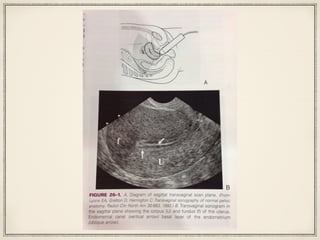

Orientation of TV probe (manoeuvres)

Rotation 0 to 90 degrees about its longitudinal

axis from capital to coronal

Sagittal plane:

Cervix, endocervical canal

Post cul de sac

Uterus and endometrium

Right ovary and adnexa

Left ovary and adnexa

Coronal plane:

Vagina

Cervix and post cul de sac

Uterine corpus and endometrium

Uterine fundus and endometrium

R ovary and L ovary and adnexa